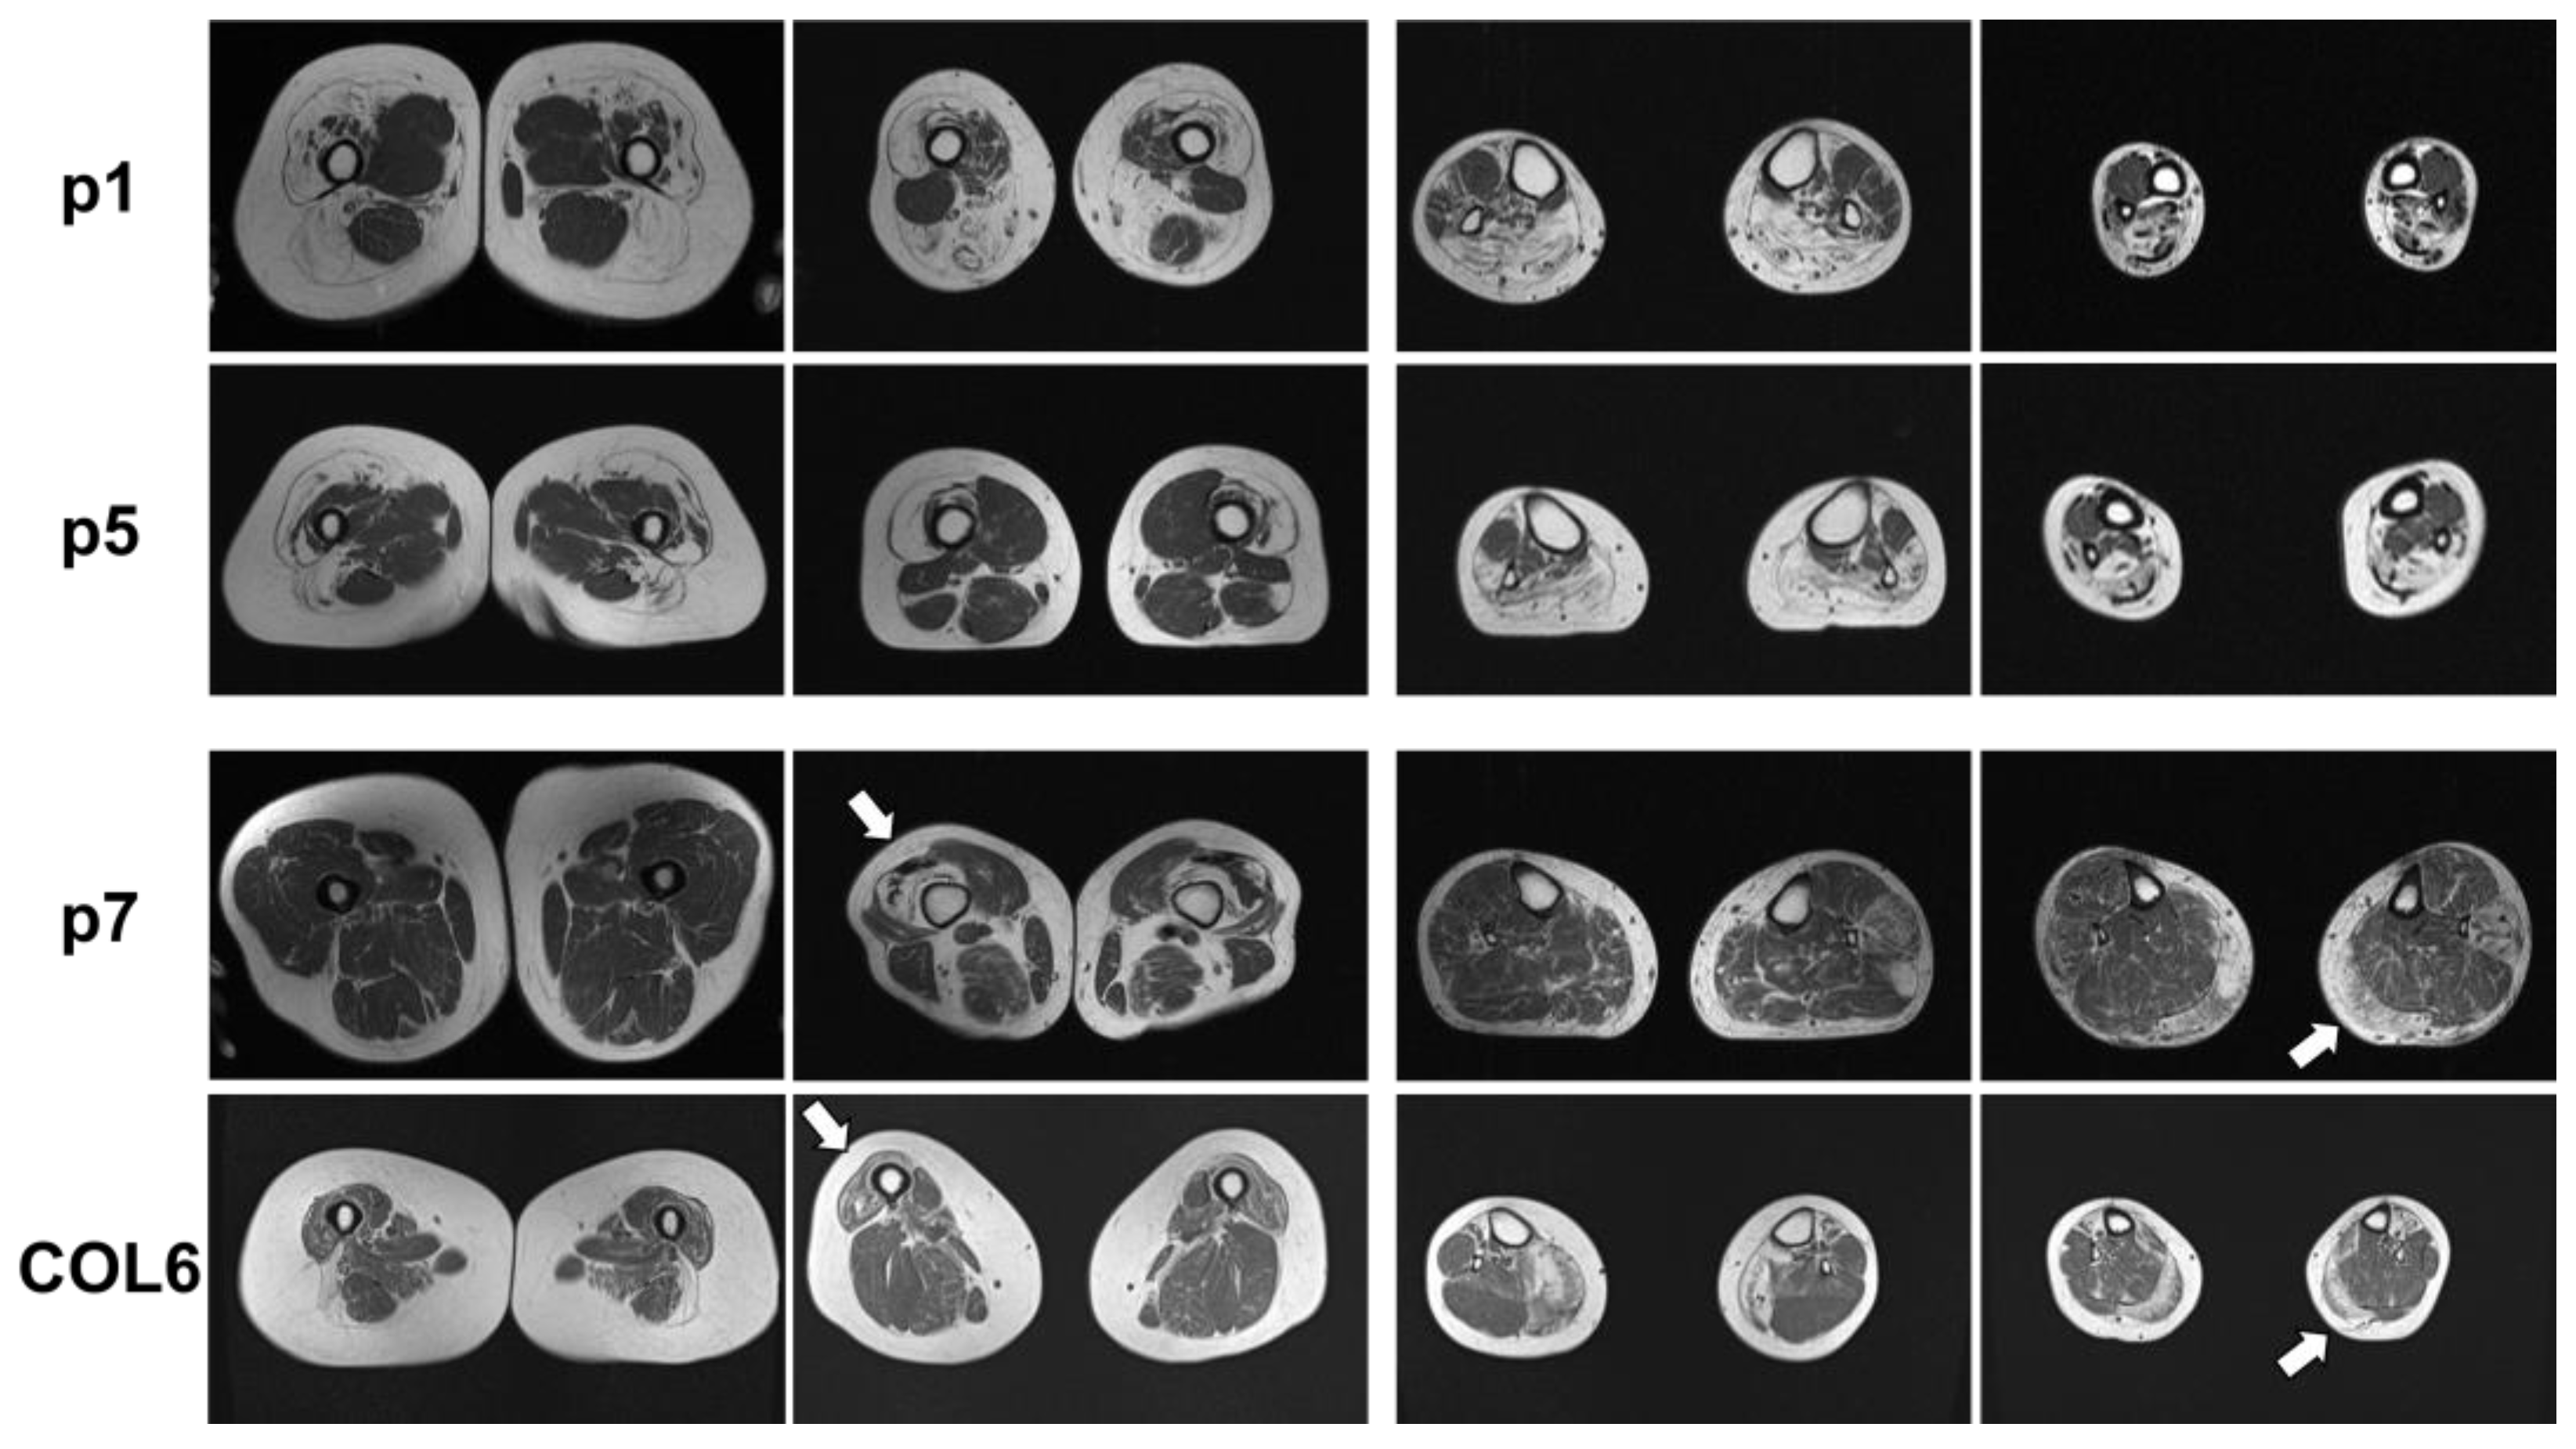

2.1. Clinical and MRI Features of Patients with BICD2-Associated Myopathy Reveal Typical Pattern of Muscle Weakness of the Legs (with Sparing of Adductor Muscles)

| p7 | BICD2: heterozygous c.2452A>G; p.(Lys818Glu), COL6A1: heterozygous c.1694G>A; p.(Arg565Gln) | Late adulthood | Proximal paresis of the lower limb muscles | Thigh muscles | 200–300 U/L |